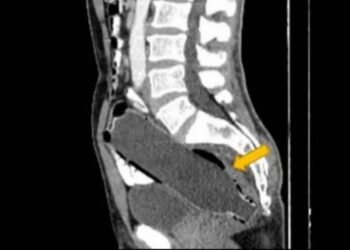

IRÃ | Um homem de 50 anos, que não teve a identidade revelada, foi levado a um hospital com constipação pela esposa, ...